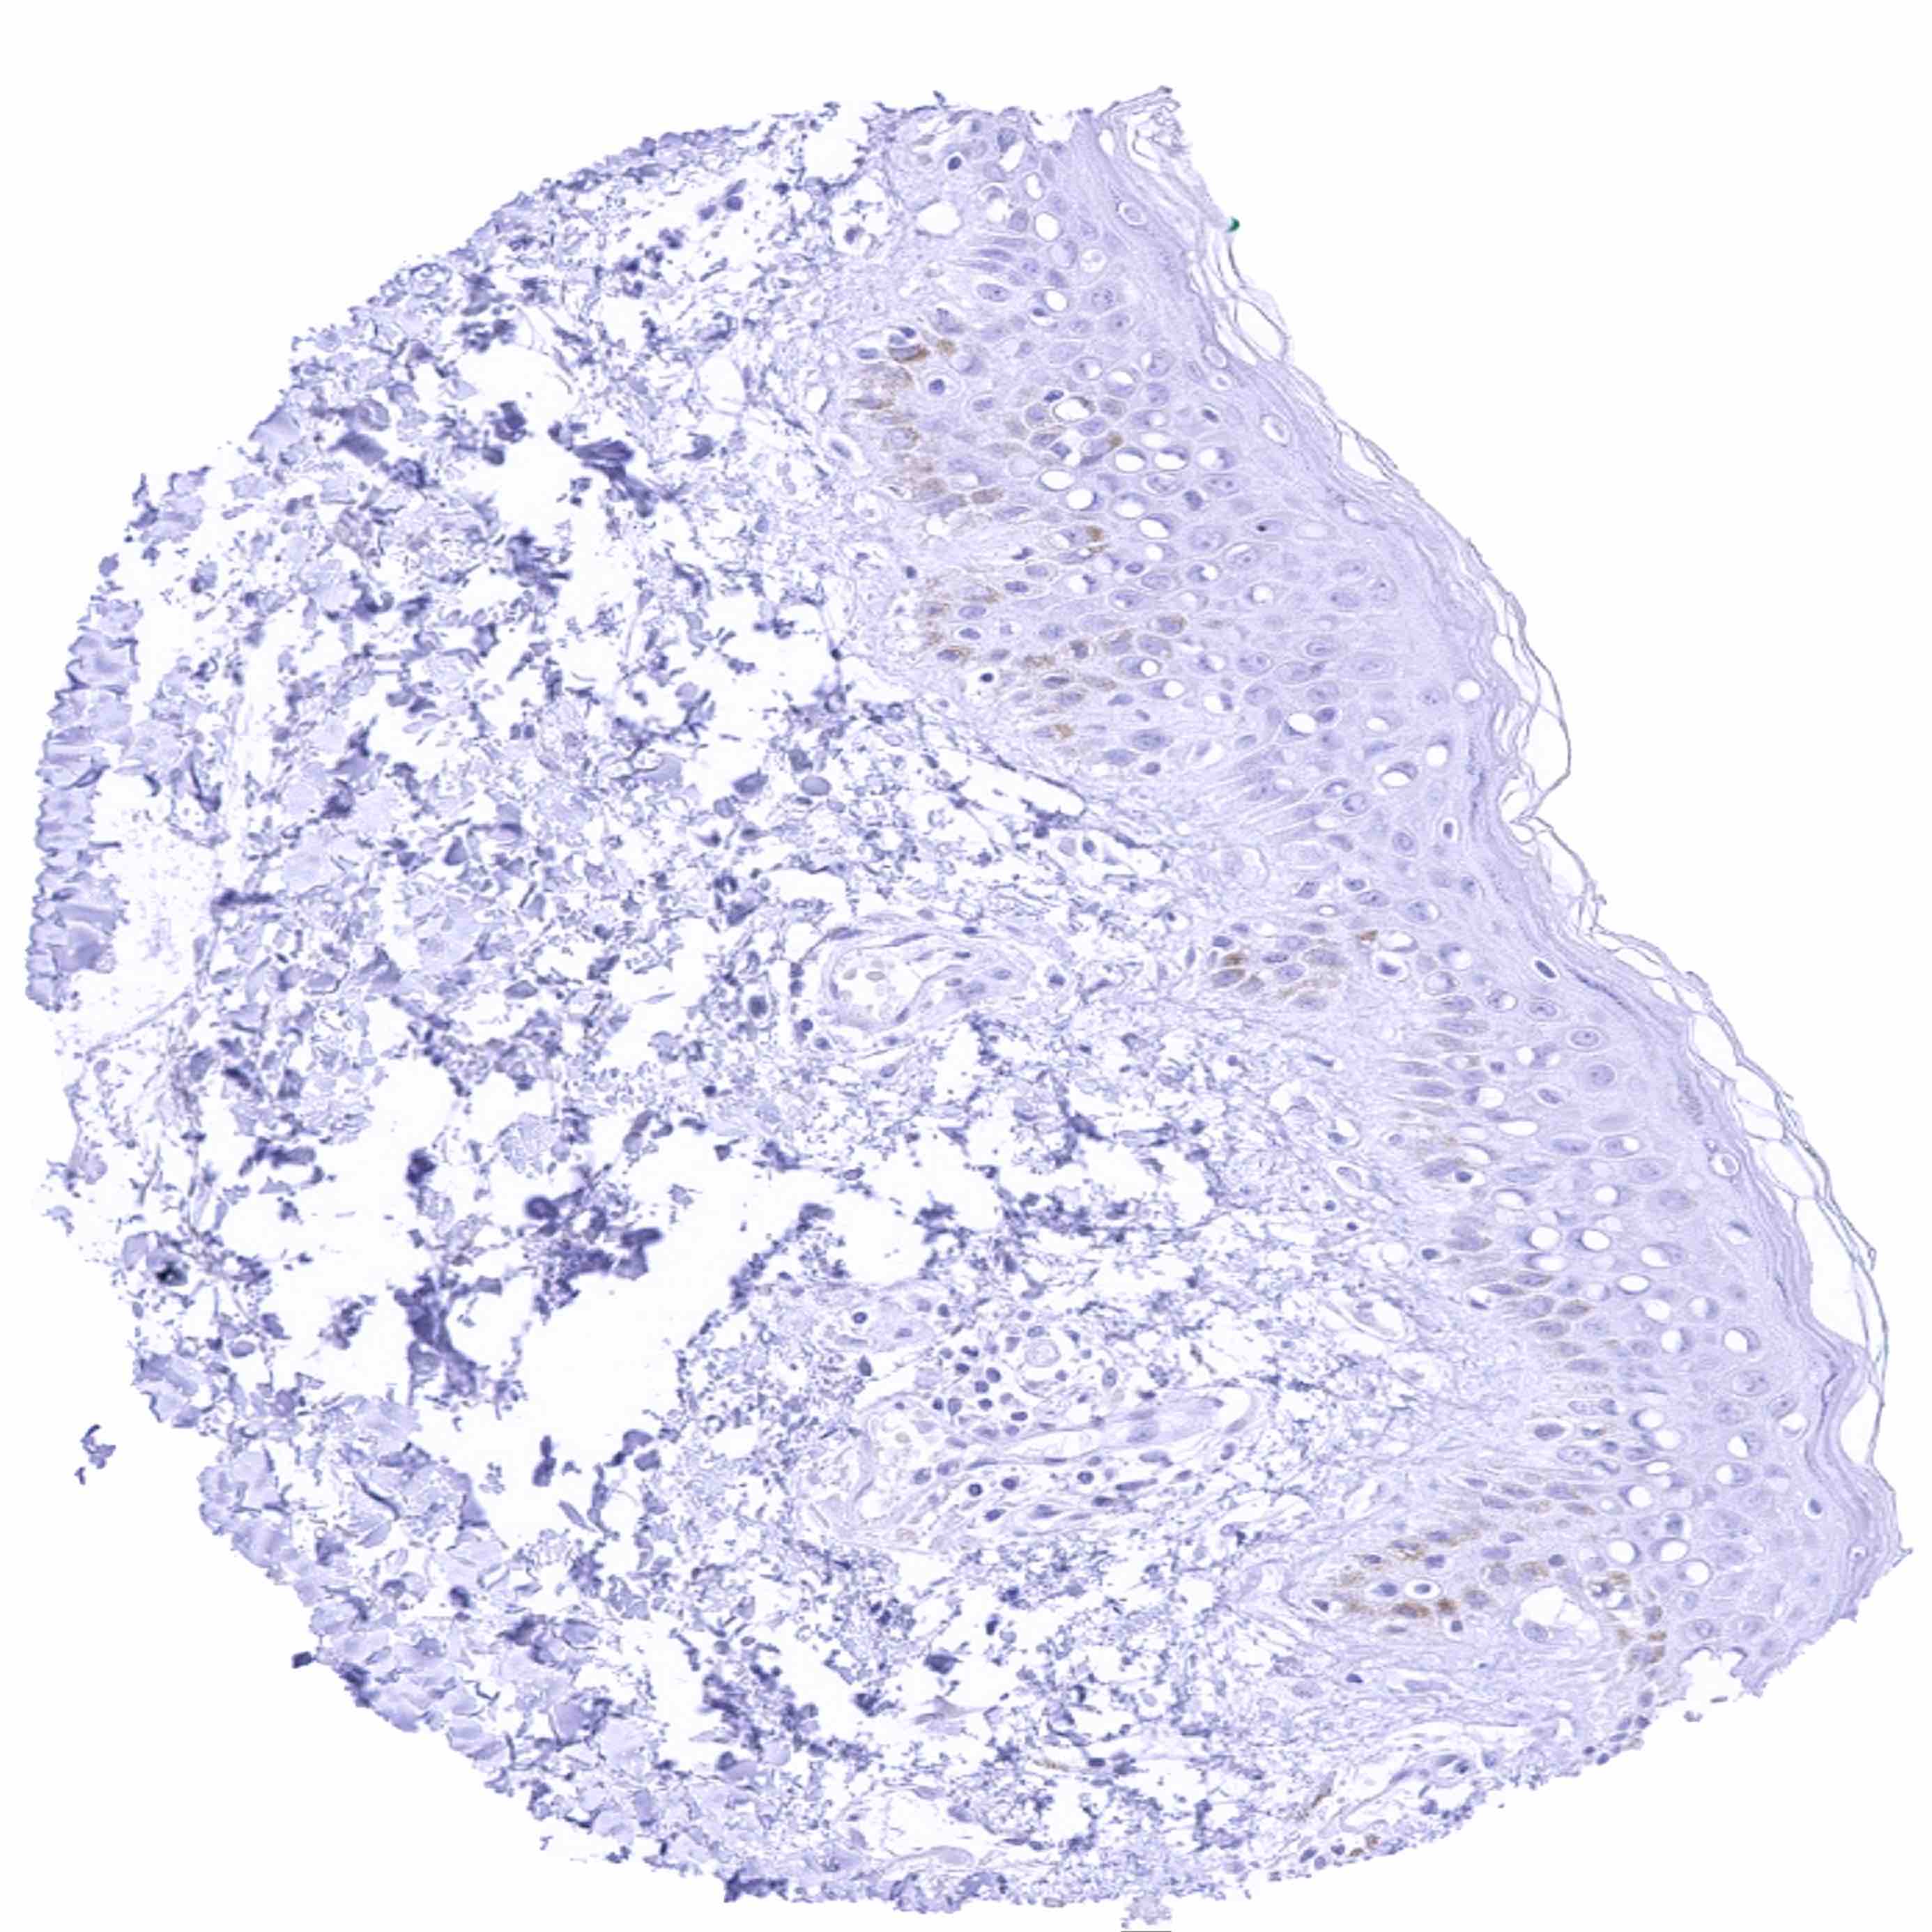

Skin

Skin, hairfollicel and sebaceous glands